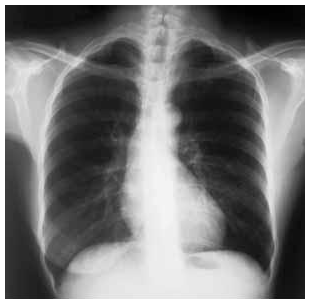

Uma mulher com 68 anos de idade foi atendida no ambulatório de um posto de saúde, com relato de tosse produtiva com

expectoração mucoide, que vem ocorrendo há mais de três anos. Informou ser tabagista (45 maços/ano) e que, nos últimos seis meses,

passou a ter dispneia progressiva aos esforços físicos. O exame físico mostrou: paciente dispneica leve, acianótica, pressão arterial de

120 mmHg × 80 mmHg, frequência cardíaca de 80 bpm, frequência respiratória de 22 irpm, com ritmo cardíaco regular em 2 tempos,

bulhas cardíacas hipofonéticas e ausência de sopros à ausculta cardíaca, diâmetro anteroposterior da caixa torácica aumentado, presença

de hipersonoridade à percussão do tórax e murmúrio vesicular reduzido de forma difusa, com roncos esparsos à ausculta pulmonar; o

restante do exame não apresentou anormalidades. Abaixo é reproduzida a radiografia do tórax em projeção posteroanterior realizada para

essa paciente.

Tendo por base as informações clínicas e a radiografia de tórax apresentadas, julgue os itens a seguir.